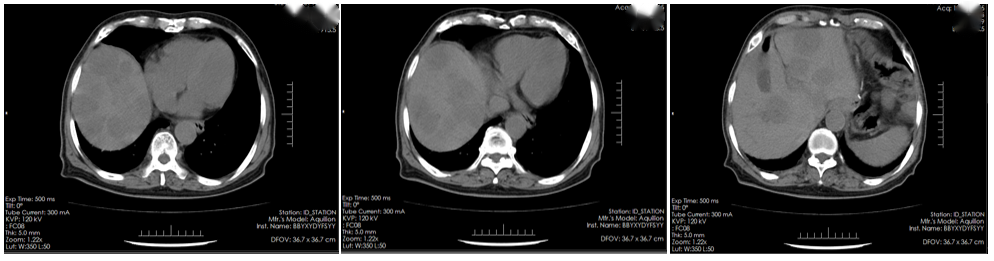

腹部CT(2023年11月6日):脂肪肝,肝内钙化灶,左肾囊肿(图1)。

17.4.png图1. 腹部CT检查(2023年11月6日)